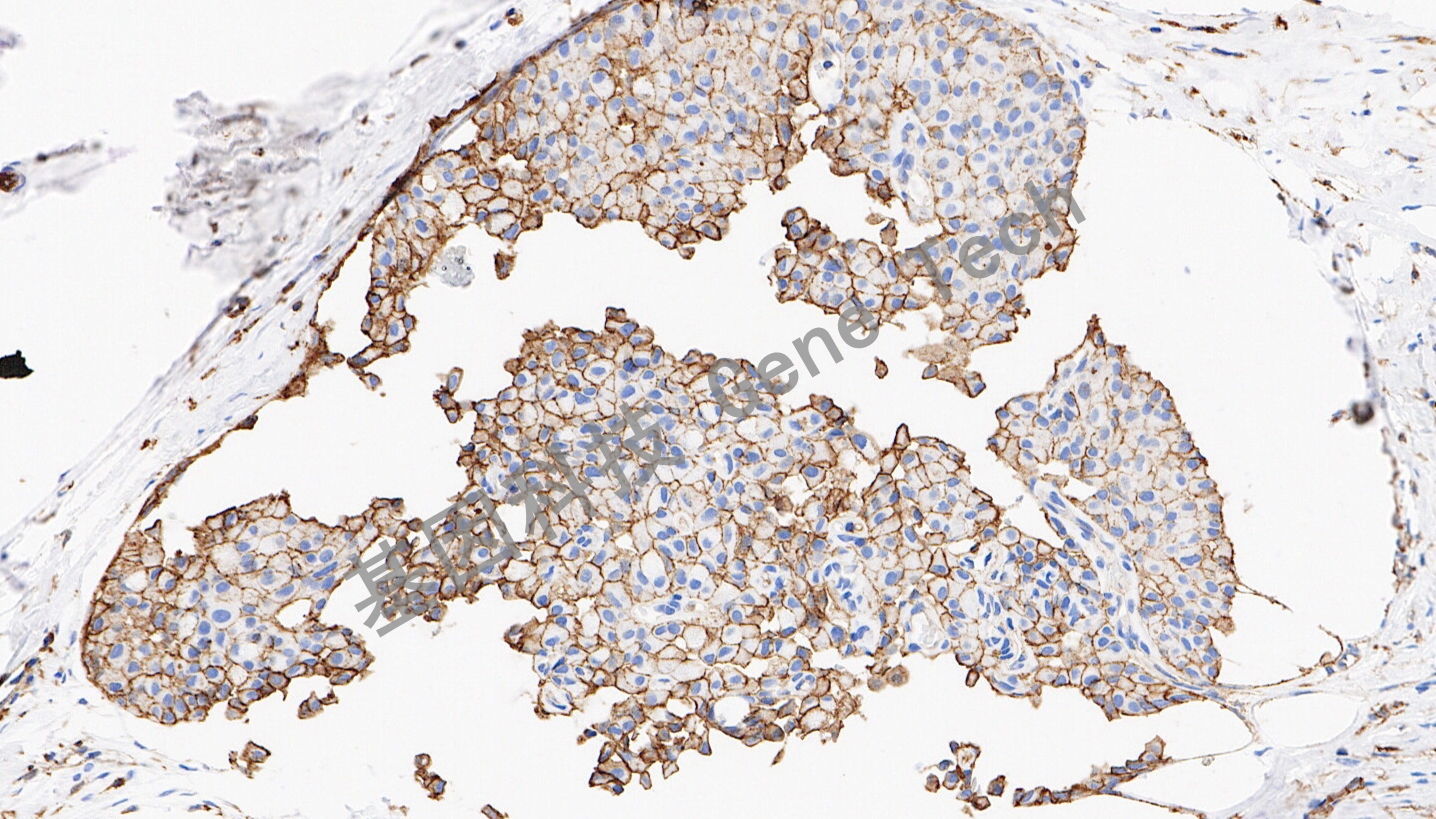

| 預處理:高pH熱修復 | 陽性部位:細胞膜 | 陽性對照:乳腺癌 |

| 乳腺癌石蠟切片,用 JAM-A (GT2598)染色,細胞膜陽性,DAB 顯色。 | ||